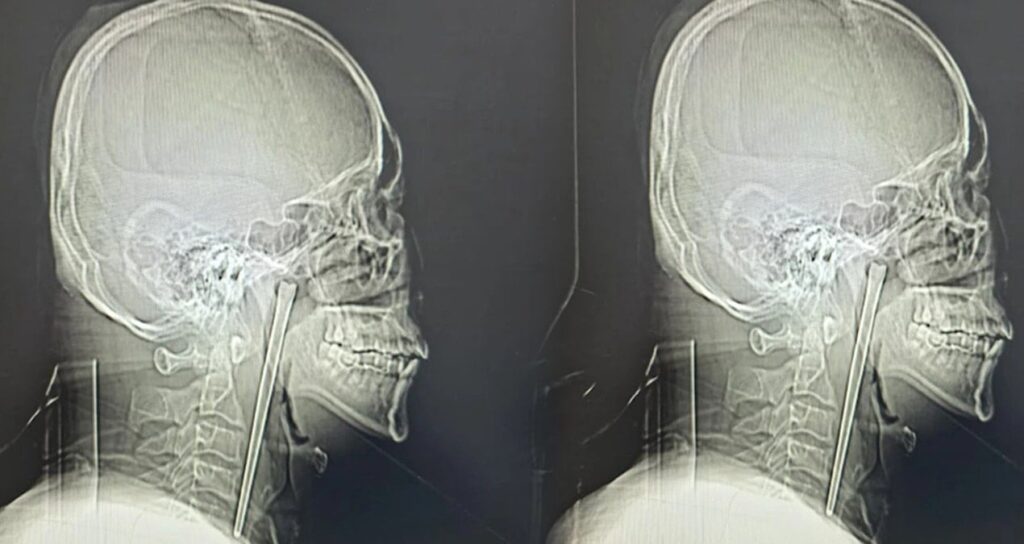

Dalian Belediye Merkez Hastanesi’nde yapılan röntgen muayenesinde, hastanın boğazında metal bir milin bulunduğu tespit edildi. Bay Wang, doktorların soruları üzerine, yemek yerken yanlışlıkla yuttuğu metal çubuğu sekiz yıl boyunca taşıdığını doğruladı.

Dalian Teknoloji Üniversitesi Bağlı Merkez Hastanesi Kulak Burun Boğaz Bölümü uzmanları, hayati damarlara ve mukoza dokusuna zarar verme riski bulunan bu cismi çıkarmak için minimal invaziv (kapalı cerrahi) yöntemi tercih etti. Dr. Huang Weipeng ve ekibi tarafından gerçekleştirilen operasyonla, 12 santimetre uzunluğundaki paslanmaz çelik yemek çubuğu dokulardan ayrılarak tek parça halinde çıkarıldı. Bu ilginç vaka, uzun süreli sağlık sorunlarının ihmal edilmemesi gerektiğini bir kez daha gözler önüne serdi.